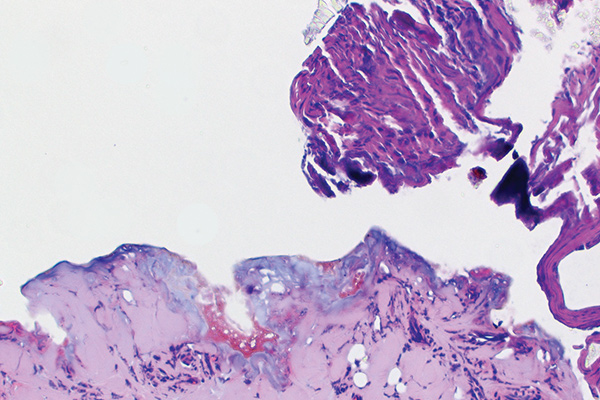

In Figure 1 through Figure 6, a variety of tissue biopsies collected via laser excision are presented. Figure 1 demonstrates the potential cellular distortion to the basement membrane region precluding detection of premalignant change. Figure 2 through Figure 4 highlight the cauterization and separation artifact caused in part by use of continuous wave versus pulsed mode. Figure 5 and Figure 6 demonstrate that by employing the advantages of laser surgical biopsy, it is possible to cleanly collect the specimen while preserving the marginal integrity of the area of suspected pathology without distortion.

Laser biopsy obliterating the squamous epithelium, because no underlying connective tissue was included (810 nm, 2.5 W, continuous wave).

Fig 4